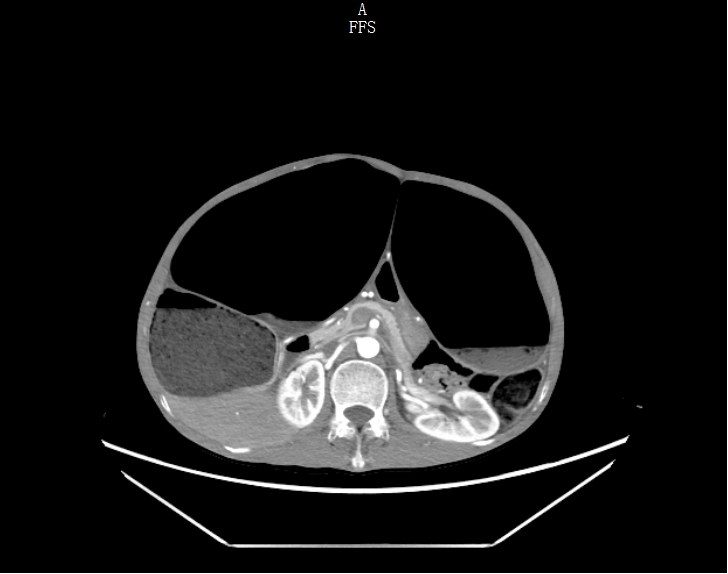

考虑到甘先生身体虚弱,无法配合完成钡灌肠大肠造影,胃肠外科·小儿外科团队给他安排了腹部 CT、DR 和肠镜检查。

结果一出来,答案清晰了:他的升结肠、横结肠显著扩张,像被吹大的气球,胀得异常粗大;可远端的结肠和直肠,却明显狭窄。

手术时发现,情况和预判的一致:回盲部、升结肠、横结肠极度扩张,降结肠、乙状结肠、直肠挛缩稍扩张,结肠内积聚大量肠液及气体。团队小心翼翼地分离粘连、切除病变结肠,每一步都精准操作,最终顺利完成手术。